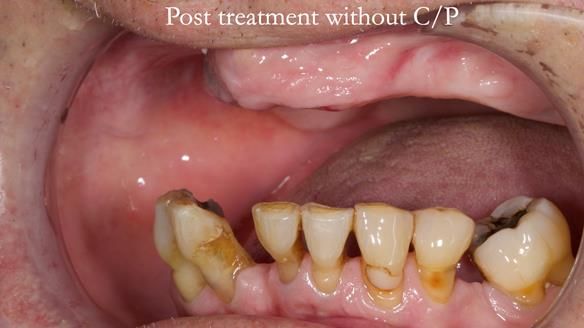

Welcome to my Newsletter 54 showing the making and fitting of dentures (a complete upper metal reinforced denture, a lower immediate partial denture and a definitive Scandinavian designed, metal based lower partial denture) for David, a 75 -year-old man. The full protocol workflow is presented including the use of dentate photographs to mimic his natural teeth.

- Missing teeth on the lower right side. This makes the upper denture tip when chewing and biting.

- The remaining lower 9 teeth had periodontal disease. Syed Abad, Specialist in Periodontics at the practice managed it.

Interestingly we found that the upper complete denture when finished and fitted didn’t have good enough retention for David’s satisfaction. It was relined by adding compound to the buccal flanges – to almost overextend into the sulcus to ‘create’ a sulcus, followed by using a light bodied silicone impression material. This improved the function of the C/-considerably. A lower Scandinavian hygienically designed lower RPD was also provided which helped with occlusal stability and reseating the upper denture – further improving the fit.